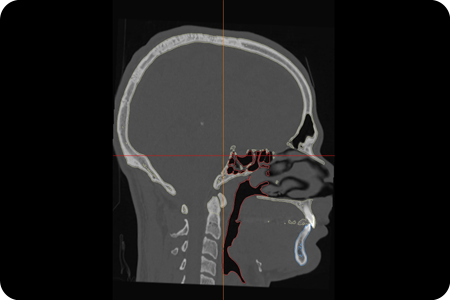

The pre-operative planning uses Materialise software – a state-of-the-art virtual Surgical Planning tool. The orthognathic surgery splints are prepared in-house, and these help position the jaws during the surgery. The use of modern technology and combined inputs from the orthodontist and the surgeon ensure predictable outcomes.